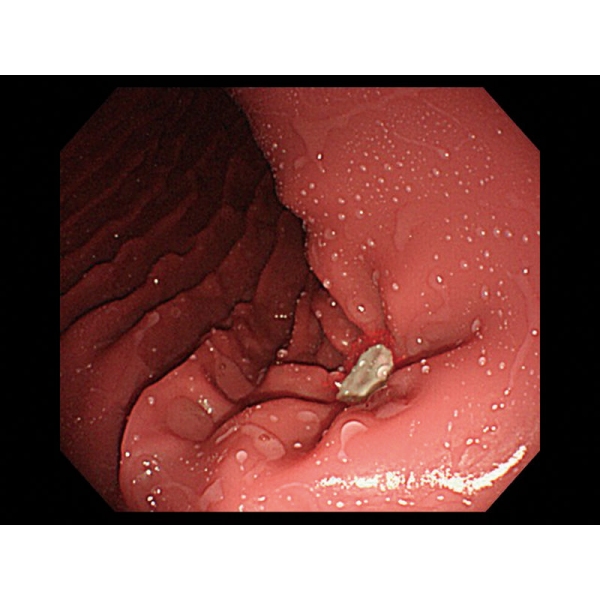

- V želodcu je mogoče opazovati želodčno razjedo in zgodnji rak želodca. Za opazovanje je mogoče pritrditi tudi štiri vrste polipov po Yamadovi klasifikaciji tipov od I do IV.

- V dvanajstniku je mogoče reproducirati razjedo.